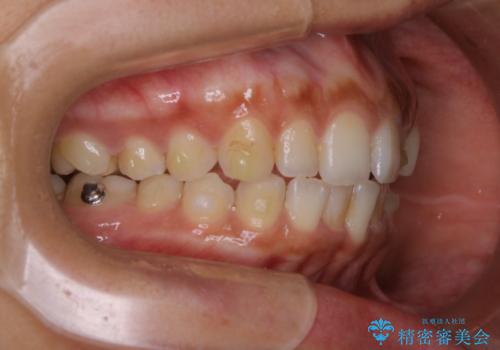

インビザライン治療中には、歯の表面にアタッチメント(効率的に歯の移動をするもの)を設定します。そのため歯ブラシでは届きにくい細かい部分などに、歯石や着色がついてしまうことがあります。着色などを放置していると、着色なのか、虫歯なのかの判別もしずらく正確にお口の中の状態を診断できません。

- インビザラインでの矯正治療中に、着色や汚れが気になるとのことでした。PMTC60分コースを行いました。